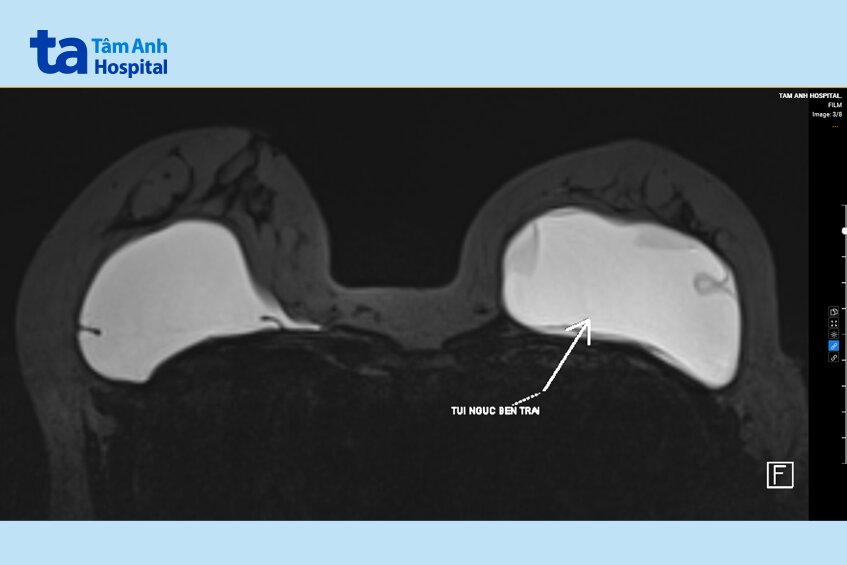

Kết quả chụp cộng hưởng từ (MRI) xác định túi ngực trái của người bệnh rách, thoái hóa trong bao. Bác sĩ chỉ định phẫu thuật tháo bỏ toàn bộ túi ngực, bóc bao xơ, lấy mẫu mô giải phẫu bệnh kiểm tra tình trạng viêm mô, u hạt (silicoma) ăn mòn mô lành.

TS.BS Hoàng Thị Phương Lan, Phòng khám phẫu thuật thẩm mỹ và Chấn thương chỉnh hình, cho biết vết rách ở túi ngực trái khoảng 3mm, đáy túi tràn dịch. Bác sĩ sử dụng hệ thống hút trung tâm loại bỏ sạch silicon và dịch nhày trước khi tháo túi.